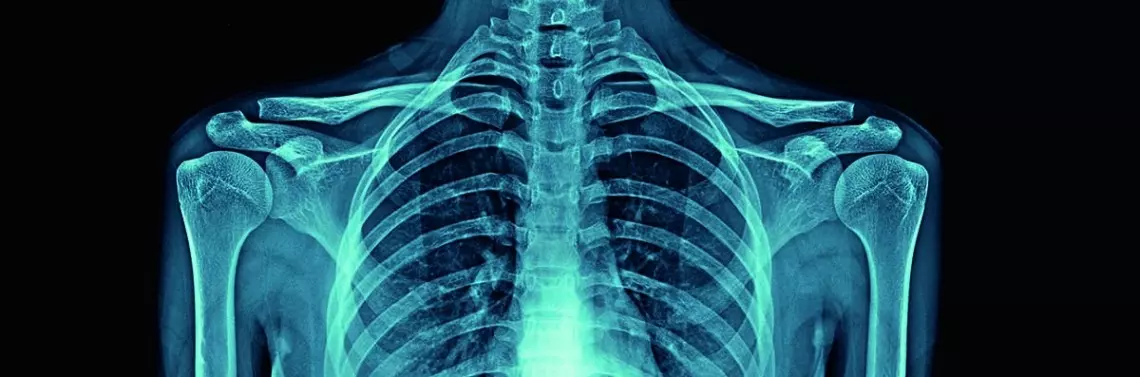

Promieniowanie radiologiczne (RTG) jest złotym standardem diagnostyki obrazowej. Jest badaniem szybkim w wykonaniu, powszechnym i niedrogim, a ukazanie rzeczywistego obrazu układu kostnego daje mu atut, którym przewyższa nowoczesne badania diagnostyczne. Zastosowanie zarówno aparatów rentgenowskich, jak i innych diagnostycznych aparatów nieinwazyjnych ma swoje zasady, cele i wzajemnie się uzupełnia. Należy pamiętać, w jakich sytuacjach ich używać, aby wykluczyć czynnik szkodliwości w dojściu do celu, jakim jest diagnostyka pacjenta.

Promieniowanie rentgenowskie jest formą promieniowania elektromagnetycznego, podobną do światła widzialnego. Jednak w przeciwieństwie do światła ma ono wyższą energię i może przenikać przez większość obiektów, w tym przez ciało, dzięki czemu jest wykorzystywane do generowania obrazów tkanek i struktur wewnątrz ciała. Promienie przechodzące przez ciało przechodzą również przez detektor promieni rentgenowskich, którym jest klisza fotograficzna. Obrazy rentgenowskie powstające w wyniku tego procesu są nazywane radiogramami.

Istnienie tego promieniowania zostało ogłoszone w 1895 r. przez niemieckiego naukowca Wilhelma Röntgena. Promieniowanie rentgenowskie od wielu lat jest wykorzystywane w medycynie w celu obrazowania wewnętrznej struktury badanego obiektu i zdiagnozowania problemów pacjenta, np. wykrycia złamań kości, niektórych nowotworów, zapalenia płuc, niektórych rodzajów urazów, zwapnień, ciał obcych, a nawet problemów z zębami.

Promieniowaniem X (promieniowaniem rentgenowskim) można wykryć wiele schorzeń, w tym nie tylko choroby i urazy układu kostnego typu złamania [16]. Radiogramy stosuje się również u pacjentów, którzy przygotowują się do wstawienia endoprotezy stawu biodrowego, lub przy ocenie różnicy w długości poszczególnych kości długich kończyn dolnych, często w przypadku diagnostyki skolioz.

Dzięki uwidocznieniu struktur kostnych RTG ma zastosowanie w diagnozowaniu osteoporozy, która charakteryzuje się obniżeniem masy i zaburzeniami struktury wewnętrznej kości prowadzącymi do złamań [5, 7].